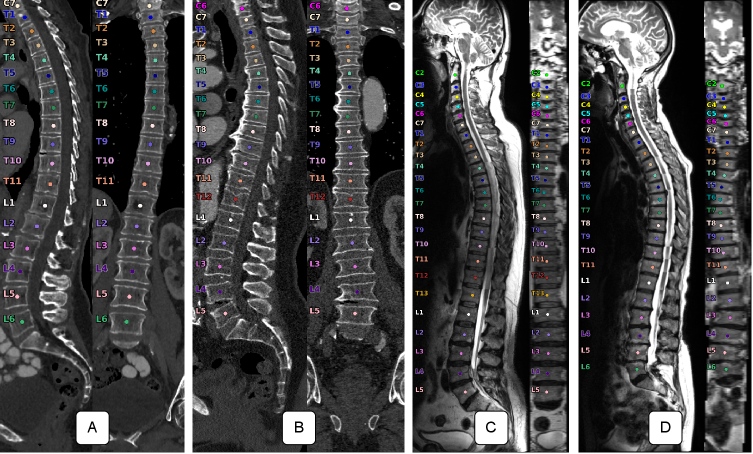

The T2w sagittal images of the NAKO always show the whole spine split into three segments and thus contain up to 26 fully visible vertebrae (see Figure 1). Using the open-source toolbox TPTBox111https://github.com/Hendrik-code/TPTBox, we stitched the different segments into one image[7]. If we now label the vertebrae in cranial-to-caudal order, we would already be correct except for TEA and LEA cases.

For CT, we utilized an in-house cohort consisting of images from various scanners. Some CT images are contrast-enhanced. The data include segmentation annotations for the vertebrae, supervised by an expert with 24 years of experience. In contrast to the T2w MRI of the NAKO, the FOV of the CTs varied heavily, containing a range of 8 – 25 fully visible vertebrae (average 16.7 3.6 vertebrae). We utilized 1536 images in which the first thoracic vertebra is present (see Figure 1). This is necessary to manually assess TEA and create the reference labels.

We demonstrate VERIDAH, a 3D vertebra labeling approach that combines multiple classification heads with a constraint optimization solver to predict vertebra labels. Our approach performs better than state-of-the-art T2w MR and CT imaging methods. VERIDAH works on arbitrary FOVs and can consistently label enumeration anomalies.